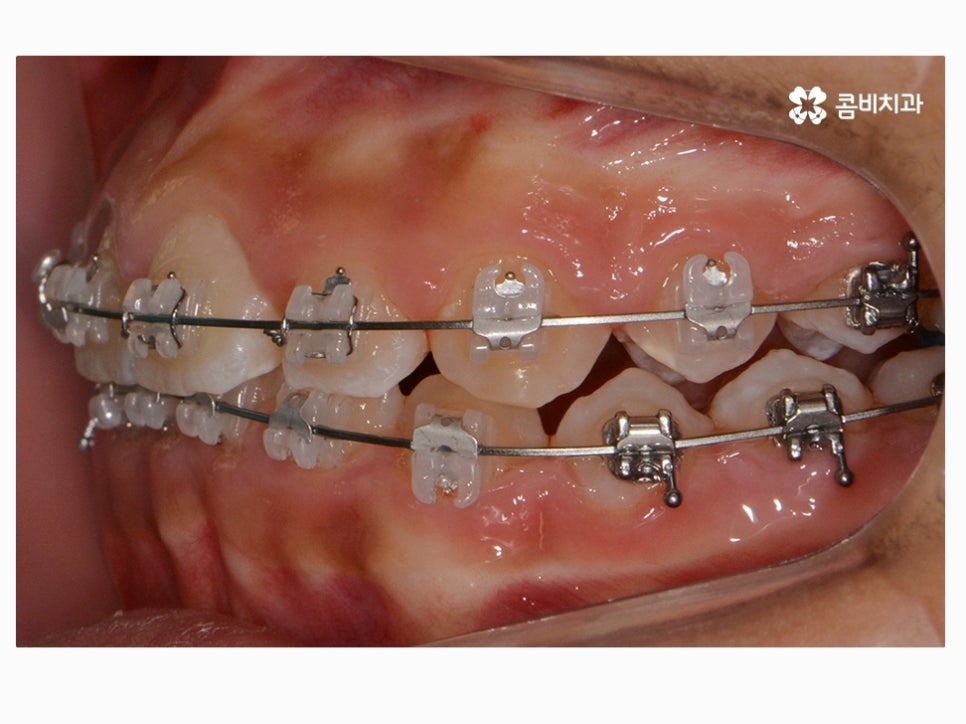

위 환자분께서 사용하신 장치는 클리피씨로 자가 결찰 장치이며

초기 통증이 줄어들고 관리가 용이하며 시술 기간을 단축시킬 수 있다는 장점이 있어요.

요즘은 이처럼 세라믹 재질을 활용하여 심미성은 높이고

교정 과정이 보다 효율적인 장치가 많이 사용되고 있는데요.